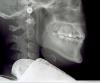

Ксюха Опубликовано 25 мая, 2011 Поделиться Опубликовано 25 мая, 2011 Уважаемые стоматологи, подскажите пожалуйста, что мне делать, не хочу потерять здоровый зуб. Начала шататься правая двойка(он под углом к десне), рядом развернутый клык. По снимкам видно, что ушла десна и образовался карман. Пародонтолог отправил к гигиенисту, где мне почистили камни ультразвуком и air flow, затем меня направили к ортодонту, который сказал, что исправить ситуацию могут только брекеты, после чего направил опять к пародонтологу чтобы мне почистили все зубы ВЕКТОРОМ(около 15 тысяч). Подскажите пожалуйста, действительно ли ВЕКТОР нужен на все зубы, или только на те, рядом с которыми образовался карман? Почему мне не предложили лоскутную операцию?Заранее благодарна за ответ. Ссылка на комментарий

Bier Опубликовано 26 мая, 2011 Поделиться Опубликовано 26 мая, 2011 мне думается, что нижнему зубу уже ничем не помочь. Ссылка на комментарий